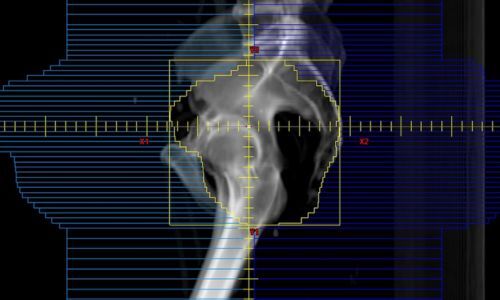

После установки всех аппликаторов пациент вновь проходит визуализационное обследование (обычно КТ или МРТ) уже с установленными устройствами. Эти новые изображения передаются в специализированную компьютерную систему планирования, где медицинский физик и онколог-радиолог разрабатывают окончательный индивидуальный план лечения.

- Контурирование: На трехмерных изображениях специалисты точно очерчивают границы целевого объема (опухоли) и всех критических органов, которые необходимо защитить (например, прямая кишка, мочевой пузырь, спинной мозг).

- Моделирование и оптимизация: С помощью программы моделируется путь движения радиоактивного источника внутри каждого аппликатора, а также время его остановки в определенных точках. Цель — достичь максимальной терапевтической дозы в опухоли, обеспечивая при этом минимальное облучение здоровых тканей. Медицинский физик рассчитывает и оптимизирует распределение дозы до тех пор, пока не будут достигнуты все заданные клинические цели. Это может потребовать нескольких итераций.

- Утверждение плана: После детального анализа и проверки план утверждается лечащим онкологом-радиологом. Этот план является "дорожной картой" для проведения сеанса облучения.